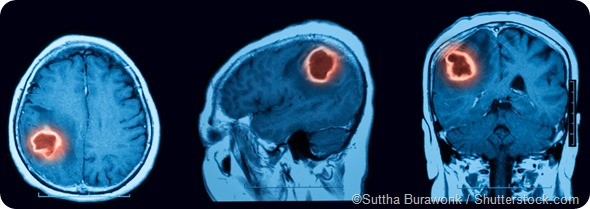

When symptoms of ICH are observed, neuroimaging should be carried out as quickly as possible - usually CT or MRI are performed. A lumbar puncture or CT angiography may also be necessary to confirm the diagnosis. Treatments include supportive care, reversal of anticoagulation therapy and surgical evacuation.

MRI scan cerebral hemorrhage